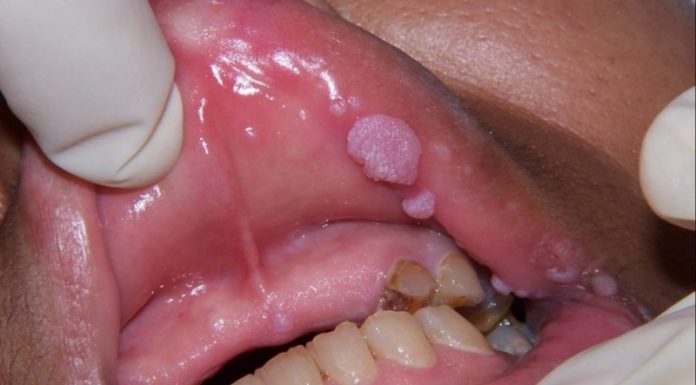

Папилломы представляют собой небольшие наросты на коже. По оттенку и размеру они могут отличаться между собой, хотя обычно речь идёт о беловатых образованиях величиной до сантиметра. Иногда также встречаются папилломы ярко выраженного коричневого цвета и наросты свыше 10 миллиметров.

Папиллома представляет собой небольшой вырост, образующийся на эпителии, похожий внешне на маленький сосочек на «ножке» или скопление приподнятых на пару миллиметров над кожей округлых новообразований. Причиной их появления является папилломовирус или, по научному, ВПЧ (вирус папилломы человека). Известно два...

Папиллома – это доброкачественное образование, появившееся в результате действия ВПЧ (вируса папилломы человека). Часто небольшие опухоли телесного цвета или немного темней обладают мягкой структурой. Они располагаются на коже или слизистой оболочке человека. Под воздействием различных факторов папилломы могут увеличиваться...